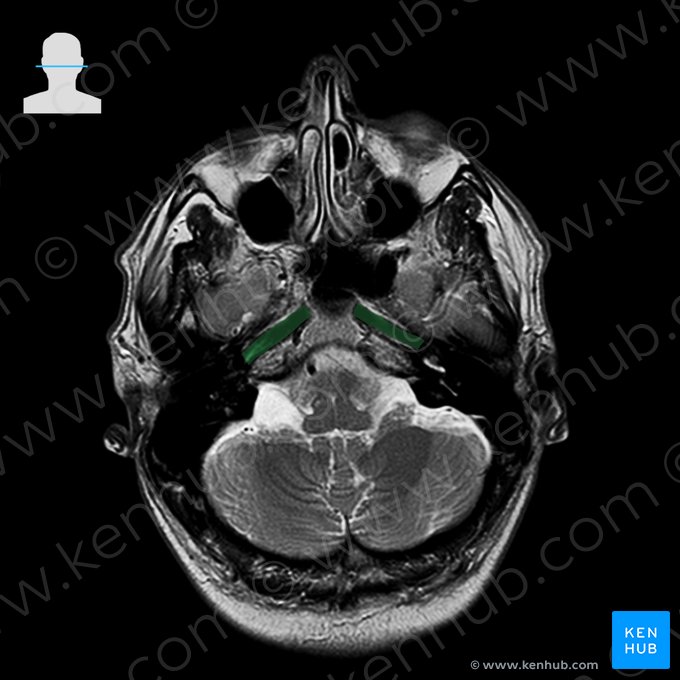

One of the most important sequences for brain imaging is one called T2-weighted sequence. On T2-weighted images cerebrospinal fluid (CSF) - or any type of clear fluid - shows a marked hyperintensity (white color), while still allows for a fair differentiation between the gray and white matter of the brain.

The following images will show you some of the anatomical structures that are identifiable with T2-weighted MRI of the brain.